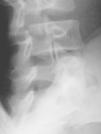

El nou estudi radiogràfic demostra espondilòlisi L5 dreta i persistència d'integritat de l'hemiarc esquerre (figs. 5 i 6). Igualment, l'estudi radiogràfic dinàmic demostra estabilitat completa de l'articulació lumbosacra (fig. 7). Per tot això es planteja l'alta esportiva, per bé que es recomana de continuar un mes més el tractament, i ajornar la tornada a la pràctica esportiva.

Figura 6

Figura 7